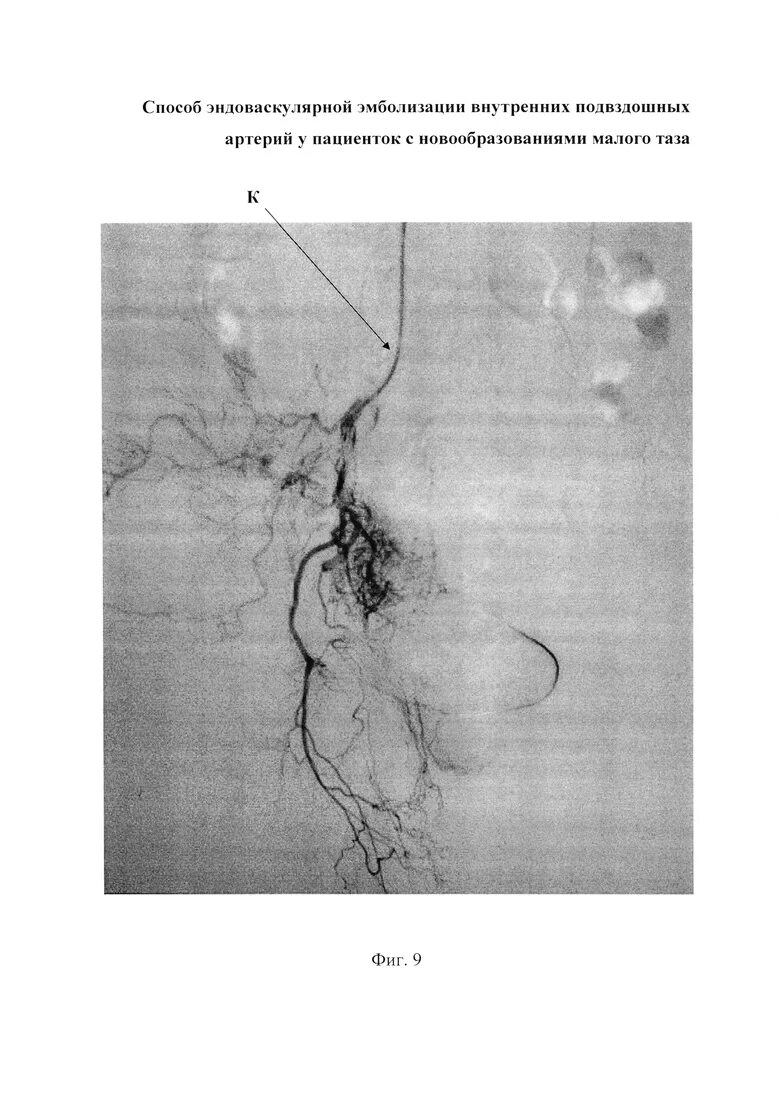

Операция эмболизации маточных артерий